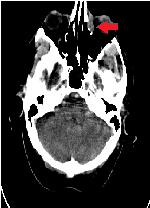

Unusual Presantatıon of Extranodal Non-Hodgkın Lymphoma: Isolated Nasolacrımal Mantle Cell Lymphoma

Ufuk Demirci1, Mine Miskioğlu2*, Aliihsan Gemici3, Nalan Neşe4, İsmet Aydoğdu2